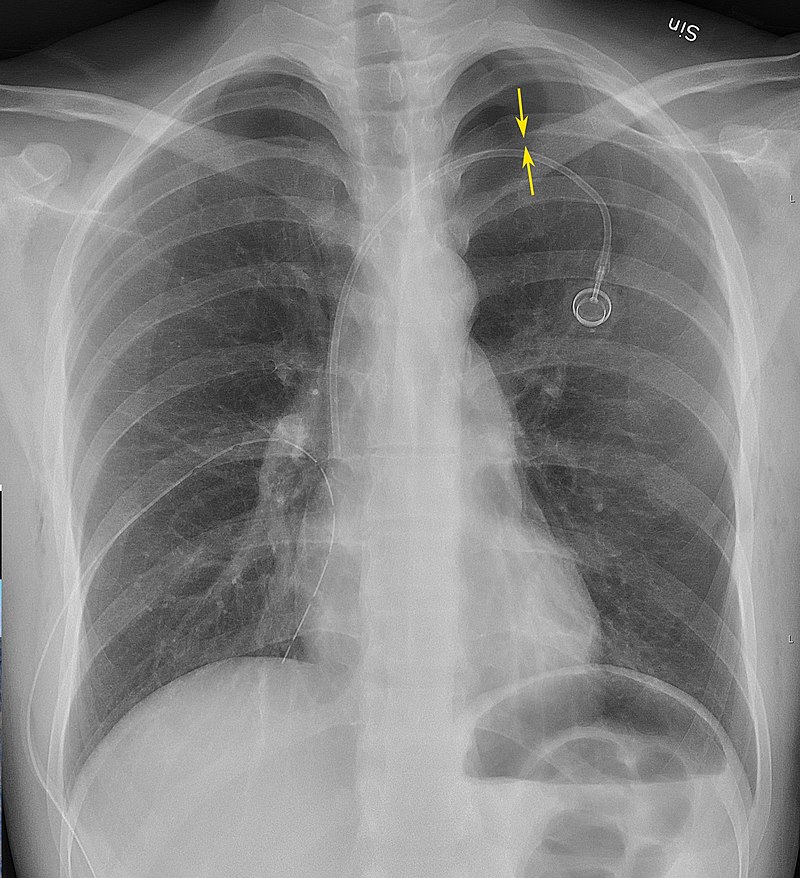

When there is a penetrating chest wound, tension pneumothorax develops.

The pleural gap allows air in but not airflow.

The trachea is pulled in the opposite direction of the wound.

Pneumothorax is a medical emergency.

Pneumothorax is treated by inserting a chest tube.